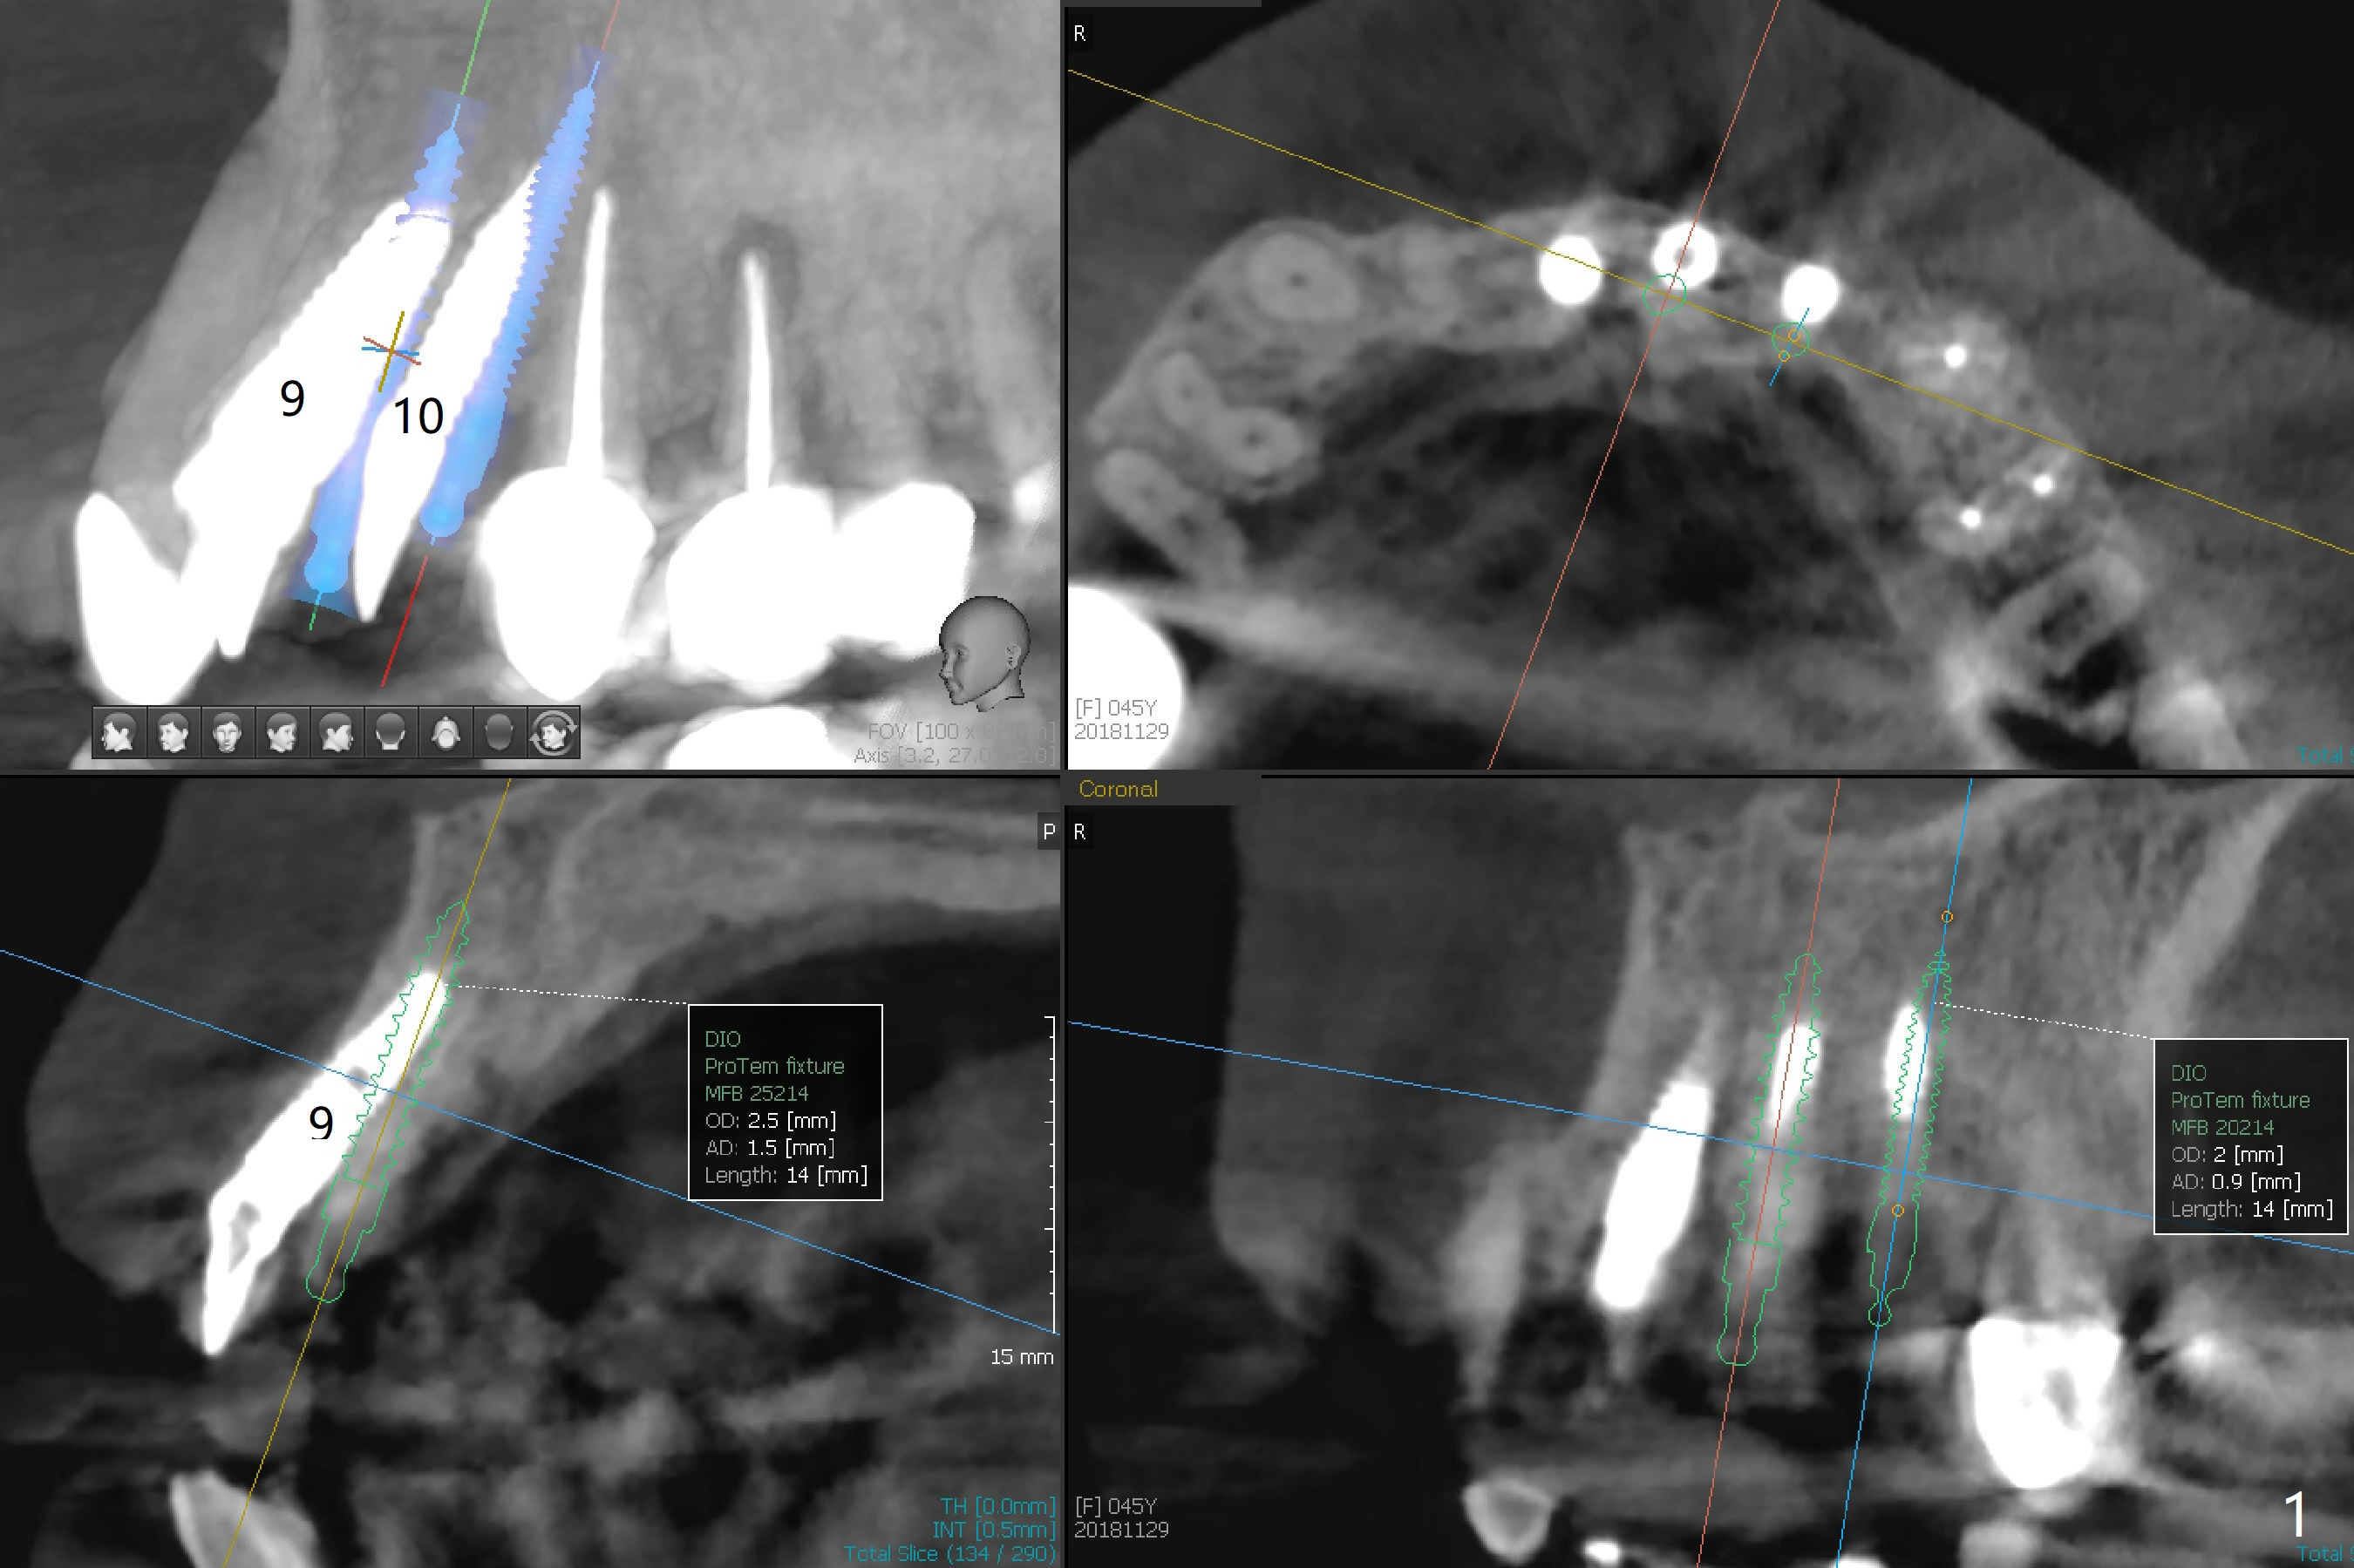

The 45-year-old woman does not like the protrusive crown at #9 as well and requests redo (Fig.1,2). A 2.5x14 mm 1-piece implant will be placed with guide immediately post removal to prevent post-removal buccal plate atrophy.